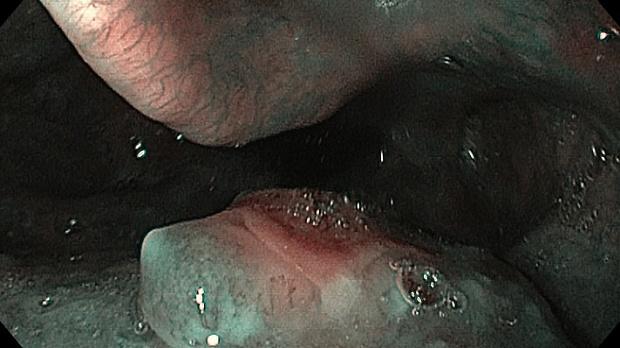

Мужчина, 63г. Жалобы на наличие плотного опухолевидного образования в подчелюстной области.

При осмотре и пальпации - образование (вероятней всего л/у), ориентировочным размером 1,5 * 2,5 см, плотное, практически неподвижное, безболезненное.

Терапевтом направлен к оториноларингологу, который патологии не нашел, дальше направлен на ЭГДС.

Вот такая картина в ротоглотке.

Из данного образования взято биопсию: плоскоклеточный рак.

В биоптате с л / у - анолигичное заключение.

Пациент без седации, что повлияло на качество эндофото.

В зоне задней стенке ротоглотки изъявленная опухоль. Чаще всего плоскоклеточная рак (основной причиной является ВПЧ).